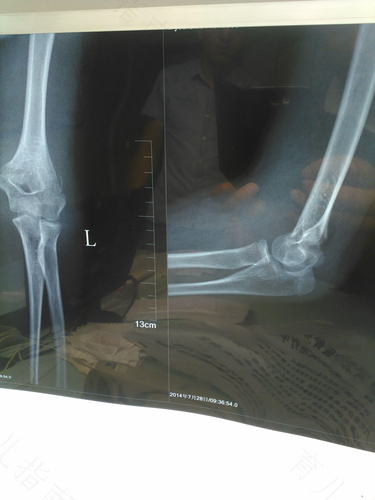

我们从小到大都会或多或少受点小伤,骨折也发生的比较多。特别是小孩子,喜欢到处乱跑乱撞,一不小心就受到伤害。很多人在及时治疗后可能会痊愈,但也有些人很担心有没有什么后遗症。比如肱骨骨折,那么左手肱骨骨折有后遗症吗?

首先,肱骨骨折多数原因是因为暴力所造成的的,有直接的也有间接的。比如被重击、摔倒时手肘撞击地面,有时候投掷物体都有可能骨折。肱骨骨折在任何年纪都有可能发生。左手肱骨骨折后,会出现局部淤青,左手臂肿胀剧痛,上臂丧事功能等。